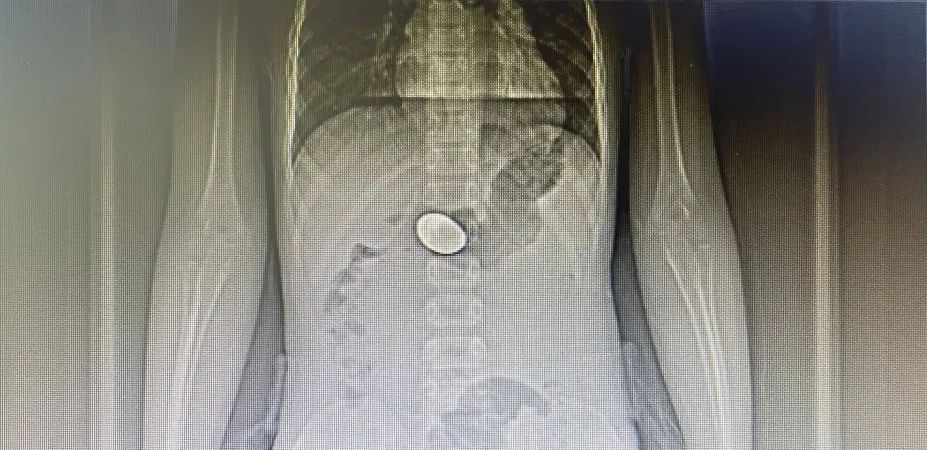

急診科醫(yī)生接診后,立即聯(lián)系消化內(nèi)科當(dāng)班醫(yī)生林炳慧醫(yī)生前來(lái)會(huì)診。林醫(yī)生仔細(xì)詢問(wèn)病史后,當(dāng)即安排小女孩做DR影像檢查,顯示食管內(nèi)未發(fā)現(xiàn)硬幣異物,在胃內(nèi)發(fā)現(xiàn)硬幣,需立即取出。

考慮到該硬幣直徑超過(guò)幽門口大小,如果長(zhǎng)期滯留在胃內(nèi),金屬異物被胃酸腐蝕,可能會(huì)導(dǎo)致金屬中毒,后果不堪設(shè)想。隨即,林醫(yī)生緊急安排為小女孩行內(nèi)鏡下胃內(nèi)異物取出術(shù)。